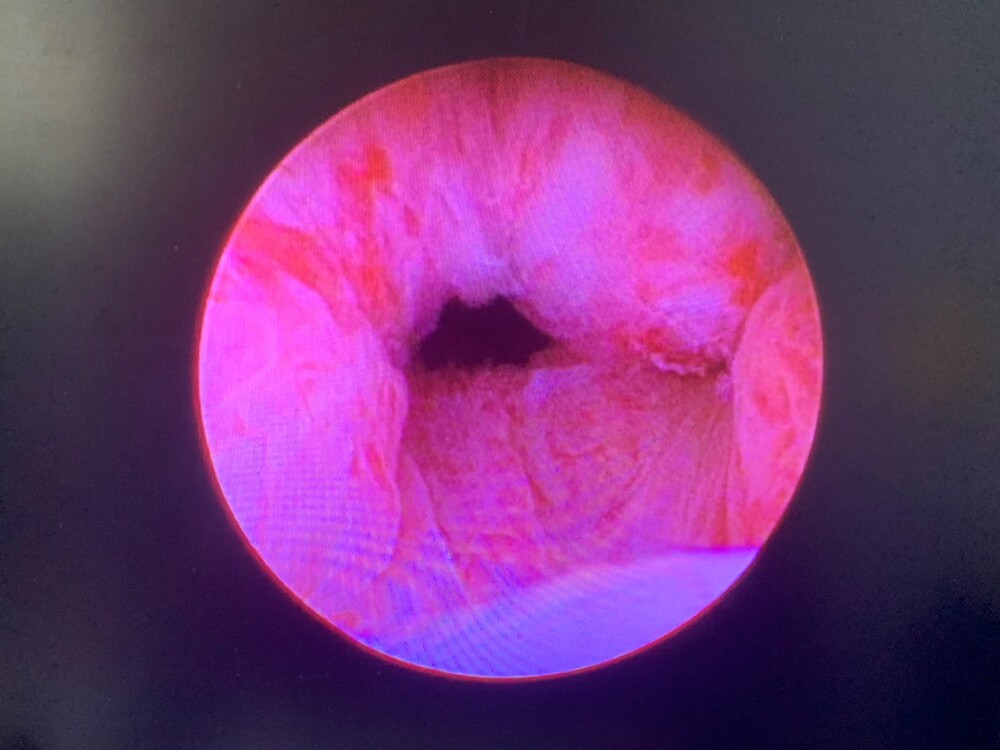

劉家翔進一步說明,攝護腺拉開手術」是一種微創、相對安全的新選擇。此手術是經由內視鏡,將鎳鈦合金的釘子植入攝護腺肥大的腺體,造成擠壓進而拉開尿路,後續攝護腺組織會因擠壓造成的缺血產生萎縮,尿路即可長期保持通暢;因為手術過程並無加熱切割或是破壞組織,所以不會造成出血、結疤,也不影響射精與勃起功能。劉家翔以生活化的例子比喻:攝護腺肥大造成尿路阻塞就像窗簾緊閉,讓光線無法透入;經過拉開手術後,窗簾完全敞開,光線完全照入室內,病人的生活也隨之明亮起來,揭開了攝護腺肥大的一線曙光。